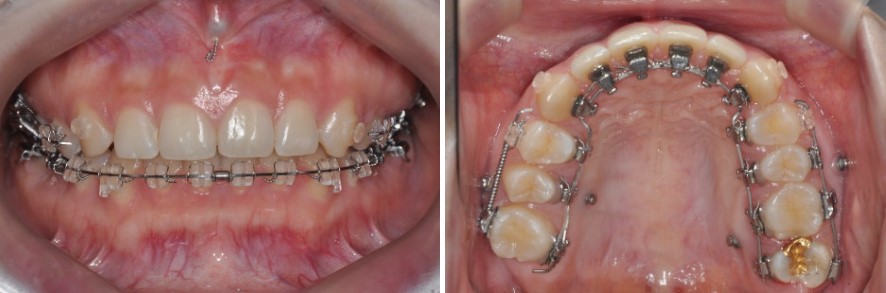

약 1년 11개월에 걸친 교정치료 끝에, 거미스마일 비발치 치료를 마무리했습니다.

먼저 구강 내 모습을 보면, 전체적인 교합이 적절하게 형성되었고,

오른쪽 위 어금니가 없는 공간으로 아래 어금니가 과도하게 올라오지 않도록 고정까지 해 둔 상태였습니다.

위·아래 어금니의 맞물림과 앞니 교합도 기능적으로 안정적인 상태로 정리되었습니다.